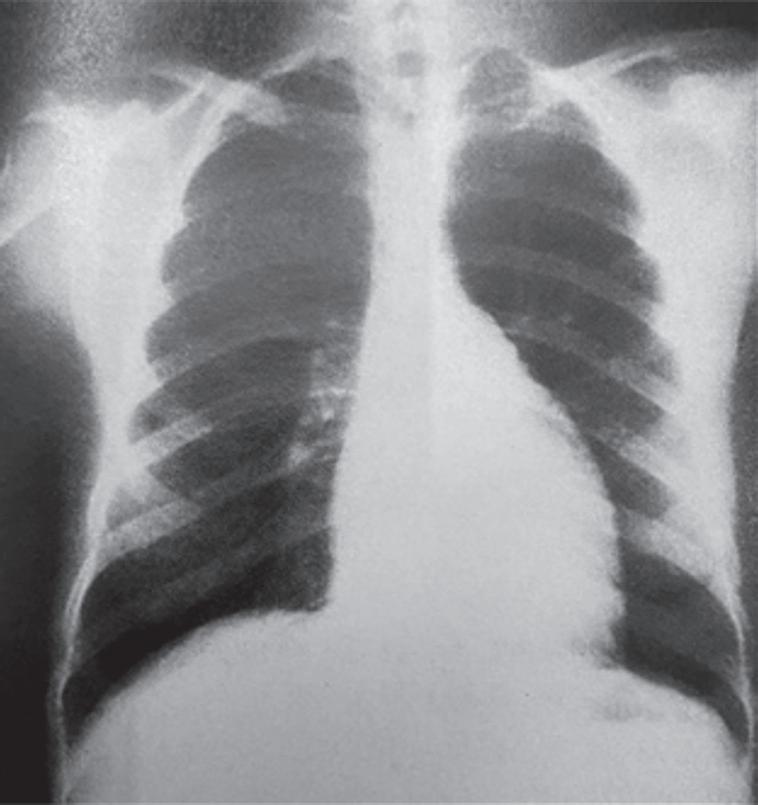

Alguns exames podem trazer outros subsídios para o diagnóstico correto dessa afecção. O eletro cardiograma apresenta alterações inespecíficas de repolarização ventricular, baixa voltagem do com plexo QRS, podendo mostrar sinais de isquemia ou pericardite. As radiografias de tórax são caracteri zadas por aumento da área cardíaca com ou sem apagamento dos vasos pulmonares, podendo apre sentar o coração em formato de moringa. O ecocardiograma transtorácico pode não ser um bom exame no pós-operatório imediato, pela dificuldade de obtenção de uma boa janela, em virtude de dre nos, dor na incisão, posicionamento impróprio do paciente e até mesmo ar na cavidade mediastinal.

Figura 10.2 (A e B) Radiografia de tórax (A) e eletrocardiograma (B) de paciente com tamponamento no pósoperatório imediato